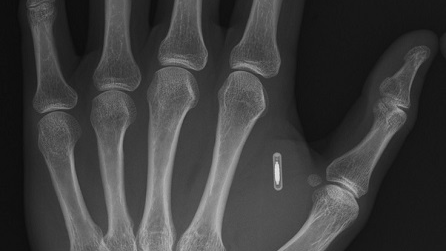

Как мы используем RFID в повседневной жизни

RFID - технология, повсеместно применяющаяся во многих областях. Многие люди используют её каждый день, даже не замечая этого. Её суть заключается в считывании или записывании данных с помощью автоматической идентификации. Сама система состоит из считывателя и метки (транспондера). Где же используется эта технология? Как эта технология может быть полезна для Вас? Не говоря о вышеперечисленных вариантах, многим будет интересно самостоятельное применение технологии в личных целях. К примеру, Вы можете...